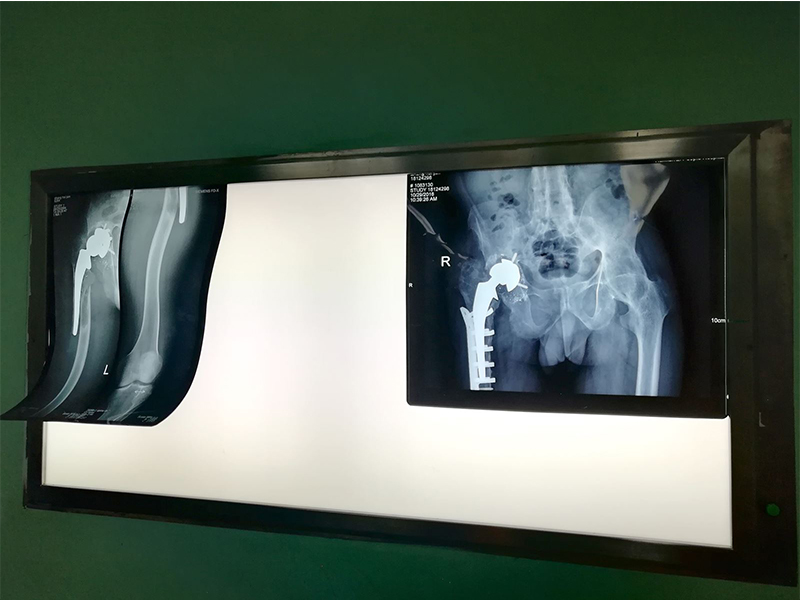

1 2 10cm